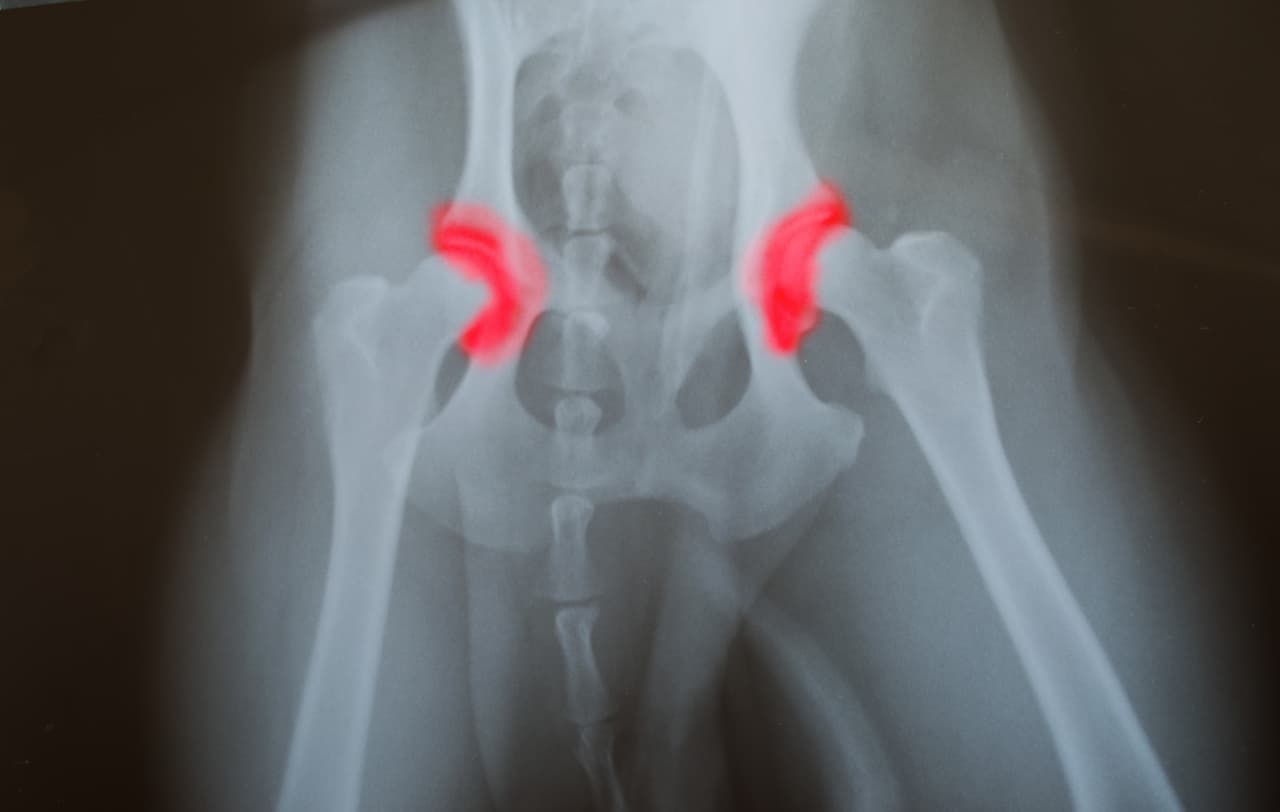

Si estiras muy rápido las piernas de tu bebé o lo colocas en una posición que fuerce la cadera, puede haber el riesgo que se deforme permanentemente la cavidad entre la cabeza femoral y el acetábulo o bien, un deslizamiento gradual que provoque una dislocación.

La institución médica Mayo Clinic llama displasia de cadera a aquella condición en la que la cavidad de la cadera no cubre completamente la parte de la cabeza del fémur superior, si ésta se diagnostica durante la infancia temprana, el problema se puede corregir con un dispositivo de inmovilización.